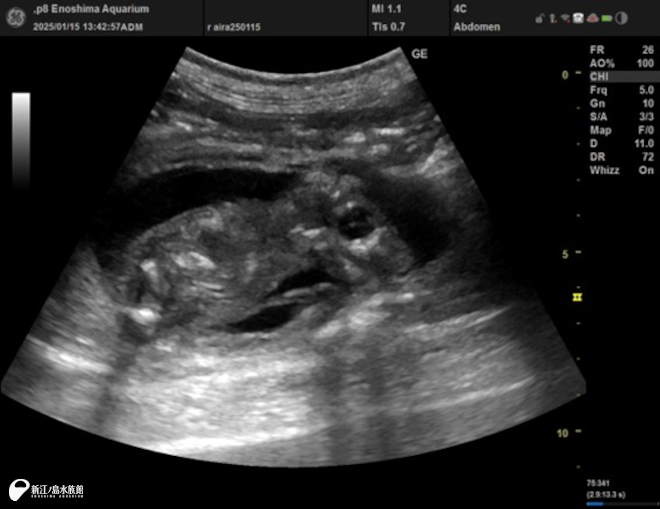

これは超音波診断装置。

高い周波数の音波を体内に照射し、組織から跳ね返ってくる反射波をリアルタイムで画像化する装置です。お腹の中にいる赤ちゃんのようすや、腸の蠕動(ぜんどう)運動、腎結石などさまざまな症状を見ることができます。

えのすいでは 3台の機器を持っていて、その時の動物の状況によって使い分けています。液晶画面が付いているものや、映像をリアルタイムにスマートフォンで見ることができるワイヤレスのものなど使用目的によって使い分けています。

2025年 1月ミナミアメリカオットセイ「ライラ」の胎子エコー。「ライム」が母「ライラ」のお腹の中にいた時の超音波画像です。胎子の成長を、超音波を使用し定期的にモニタリングしていきます。